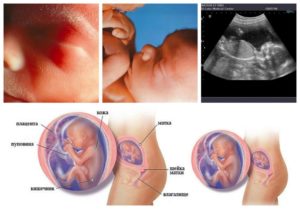

Плод на 19 неделе беременности

Размер плода в 19 недель беременности варьируется от 20 до 25 см (это длина тела). Обхват груди составляет до 44 мм. Вес уже вполне ощутим: около 250-300 г. Отныне вес ребенка в норме должен постоянно увеличиваться довольно быстрыми темпами. Самый заметный прирост веса будет наблюдаться в третьем триместре.

Размер плода, его развитие оценят на УЗИ. Зная, какой это месяц – 19 неделя беременности, вы можете почти точно сами предсказать, когда начнутся первые шевеления. Они должны начаться при первой беременности на сроке до 20 недели, второй беременности – чуть раньше.

Ребенок на 19 неделе беременности активно «обрастает» подкожно-жировой клетчаткой. Постепенно затвердевают хрящи. Формируется костная система, поэтому из материнского организма активно «вымывается» кальций. Что нужно корректировать сбалансированным питанием.

Узи на 19 неделе беременности

По УЗИ будет видно, как выглядит ребенок в 19 недель беременности. Исследование назначают, если женщина еще не прошла его в рамках второго скрининга.

Кроме того, что Узи на 19 неделе беременности позволяет точно узнать пол ребенка и определить возможные риски, врач может назвать размер и плода, и месторасположение плаценты, посмотреть, как она развивается.

Тонус матки на 19 неделе беременности также возможен – его видно на УЗИ. Если женщину беспокоит, что на 19 неделе беременности нет шевелений, – доктор назовет ей причину этого и скажет, стоит ли волноваться или можно еще спокойно подождать.

Один из факторов риска – на 19 неделе низкая плацентация. Доктор пояснит, нужно ли предпринимать какие-либо действия.